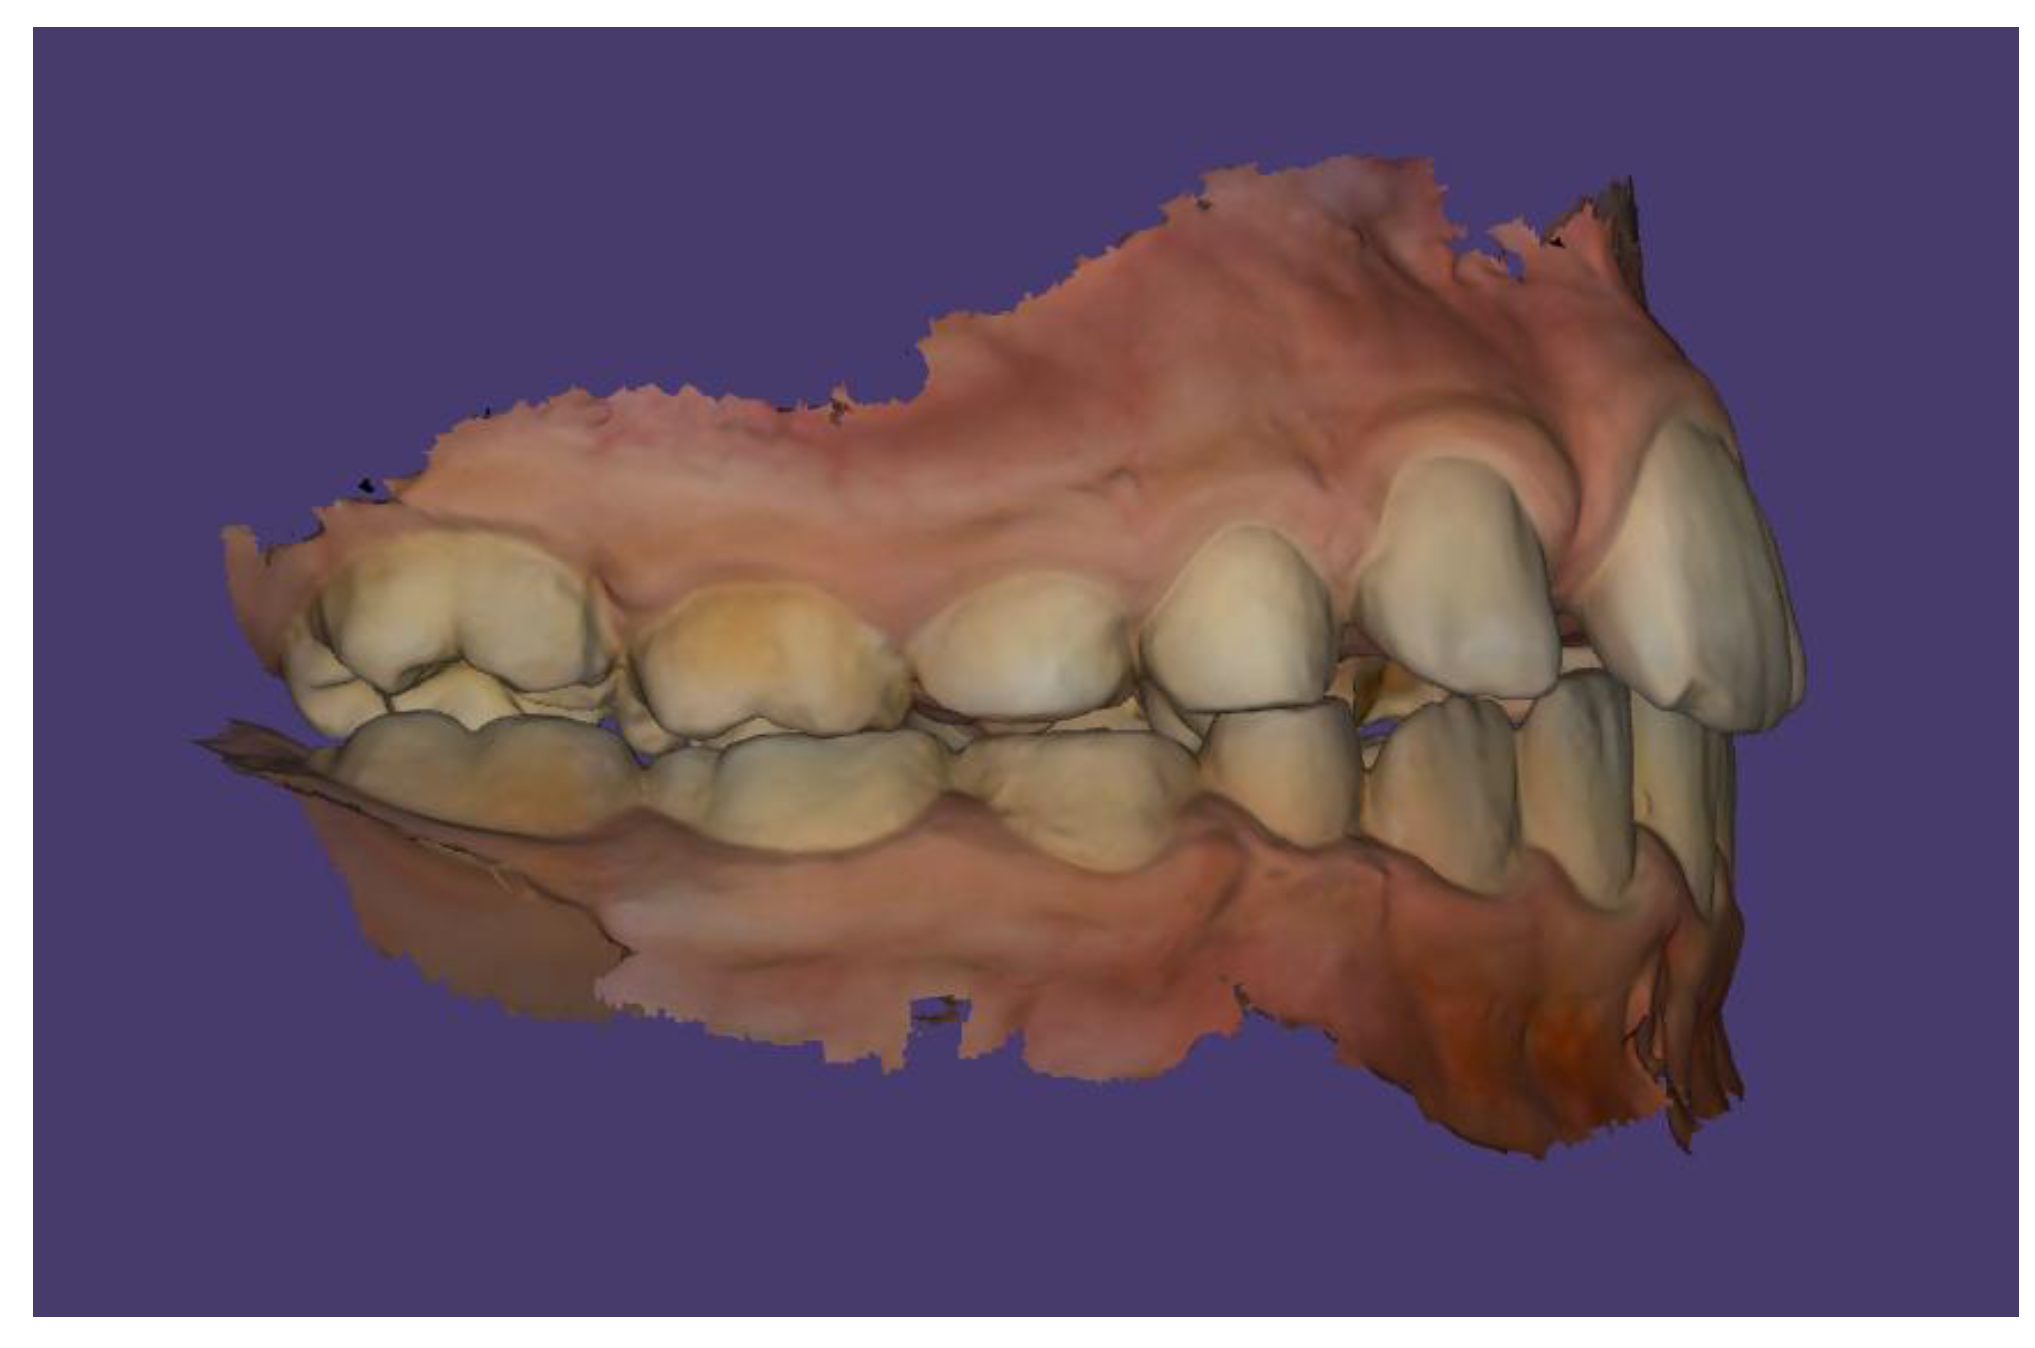

Case Description